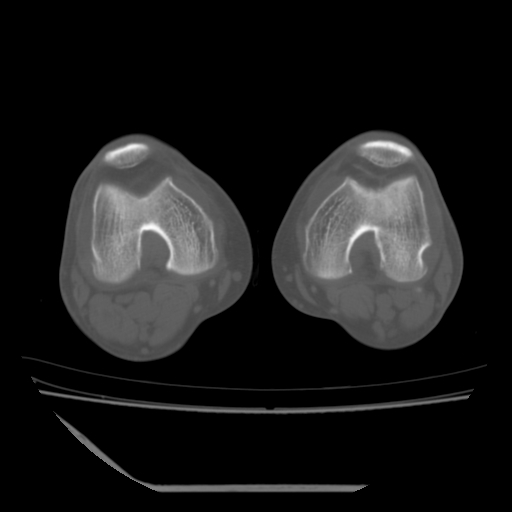

标题: CT13225:老年男性,左膝关节疼痛数月;请各位老师讨论。 [打印本页]

标题: CT13225:老年男性,左膝关节疼痛数月;请各位老师讨论。

骨质增生,骨性关节面硬化,关节积液,考虑退行性骨关节病

关节腔内少量积液,关节面退变。

双膝退变

骨质增生,骨性关节面硬化,关节间隙失常,关节积液,考虑退行性骨关节病.

骨质增生,骨性关节面硬化,关节积液,考虑退行性骨关节病。

这个病例诊断:退行性骨关节炎